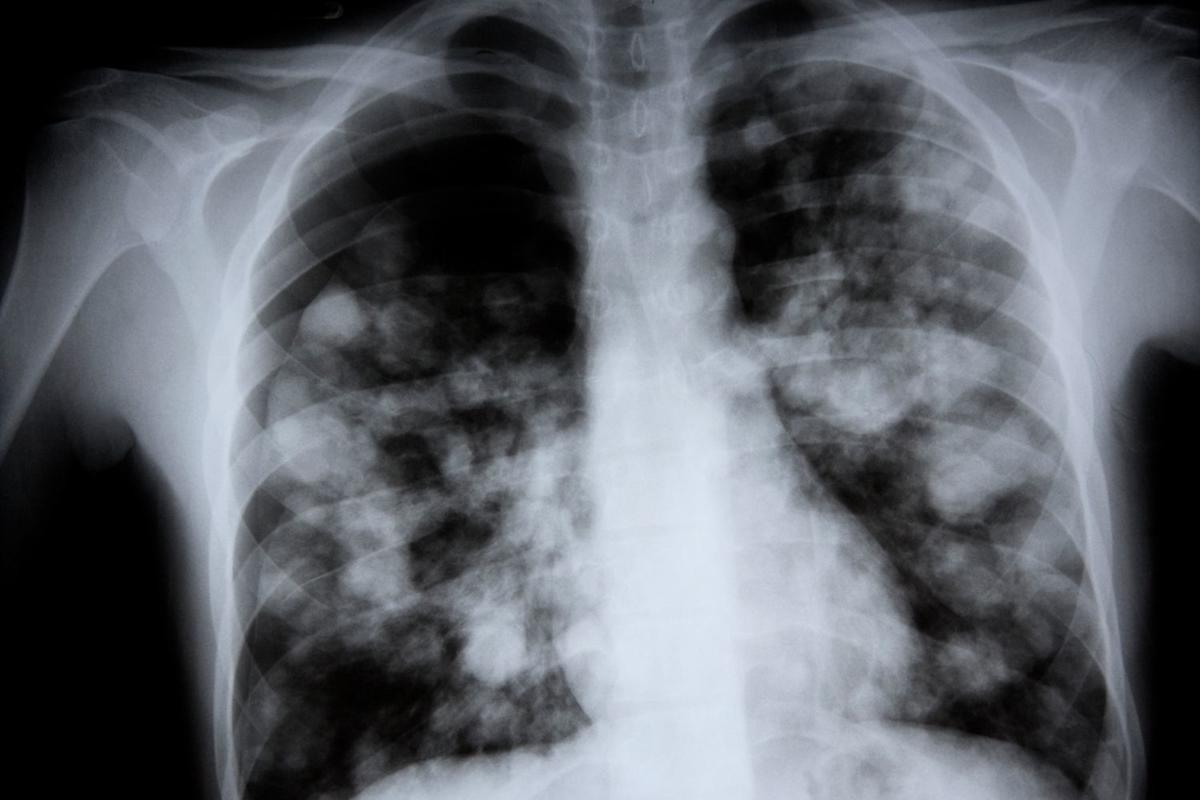

Imaging Differences

Imaging, like chest X-rays, is vital for diagnosing pneumonia. They help by:

- Confirming pneumonia.

- Seeing how much of the lung is affected.

- Finding complications like pleural effusion.

Bacterial pneumonia is diagnosed with lab tests like blood cultures and sputum analysis. Chest X-rays are also used.

Viral pneumonia is diagnosed with lab tests like PCR and serology. Chest X-rays are also used.